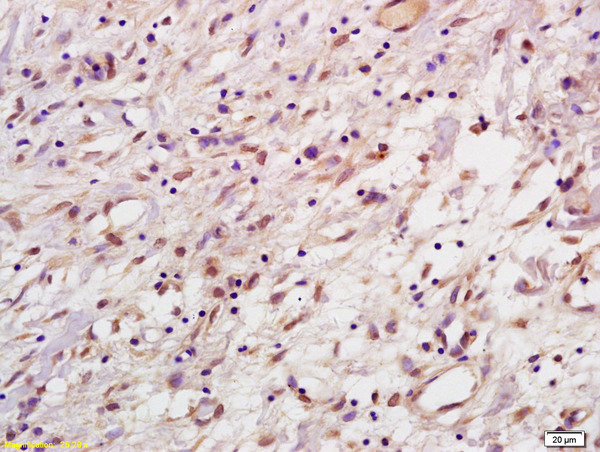

- Main image

- Experimental details

- Formalin-fixed and paraffin embedded human gastric carcinoma labeled with Anti-HPV33 E7 Polyclonal Antibody, Unconjugated (bs-2969R) at 1:200, followed by conjugation to the secondary antibody and DAB staining

- Sample type

- Human

- Other comments

- Stomach